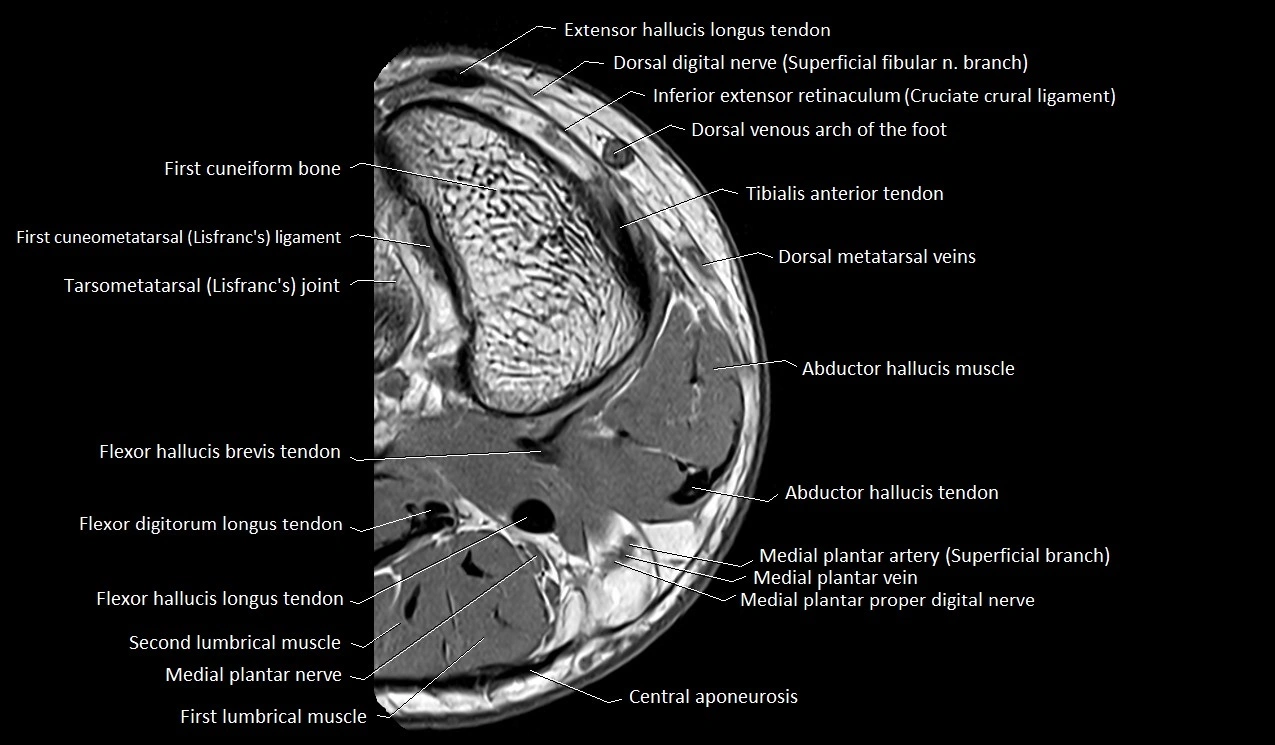

MRI image

image